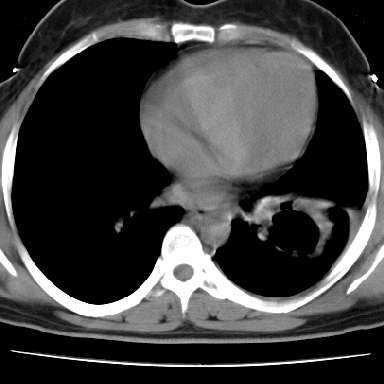

左下肺肿块影,内可以见小泡征,并见厚壁空洞形成,洞内缘凹凸不平,可见壁结节。靠近胸膜侧可见胸膜凹陷征。左侧胸腔内可见少量低密度积液影。右肺可见两处高致密的小结节影。

考虑:左下肺周围型肺癌伴右肺转移

左下肺肿块影,内可以见小泡征,并见厚壁空洞形成,洞内缘可见壁结节。靠近胸膜侧可见胸膜肥厚粘连。双肺可见多发性小结节影。

考虑:左下空洞性肺癌伴两肺转移

偏心性厚壁空洞,壁结节,胸膜肥厚粘连,双肺多发性小结节灶。这么多典型征象,即使错了也错的有道理!